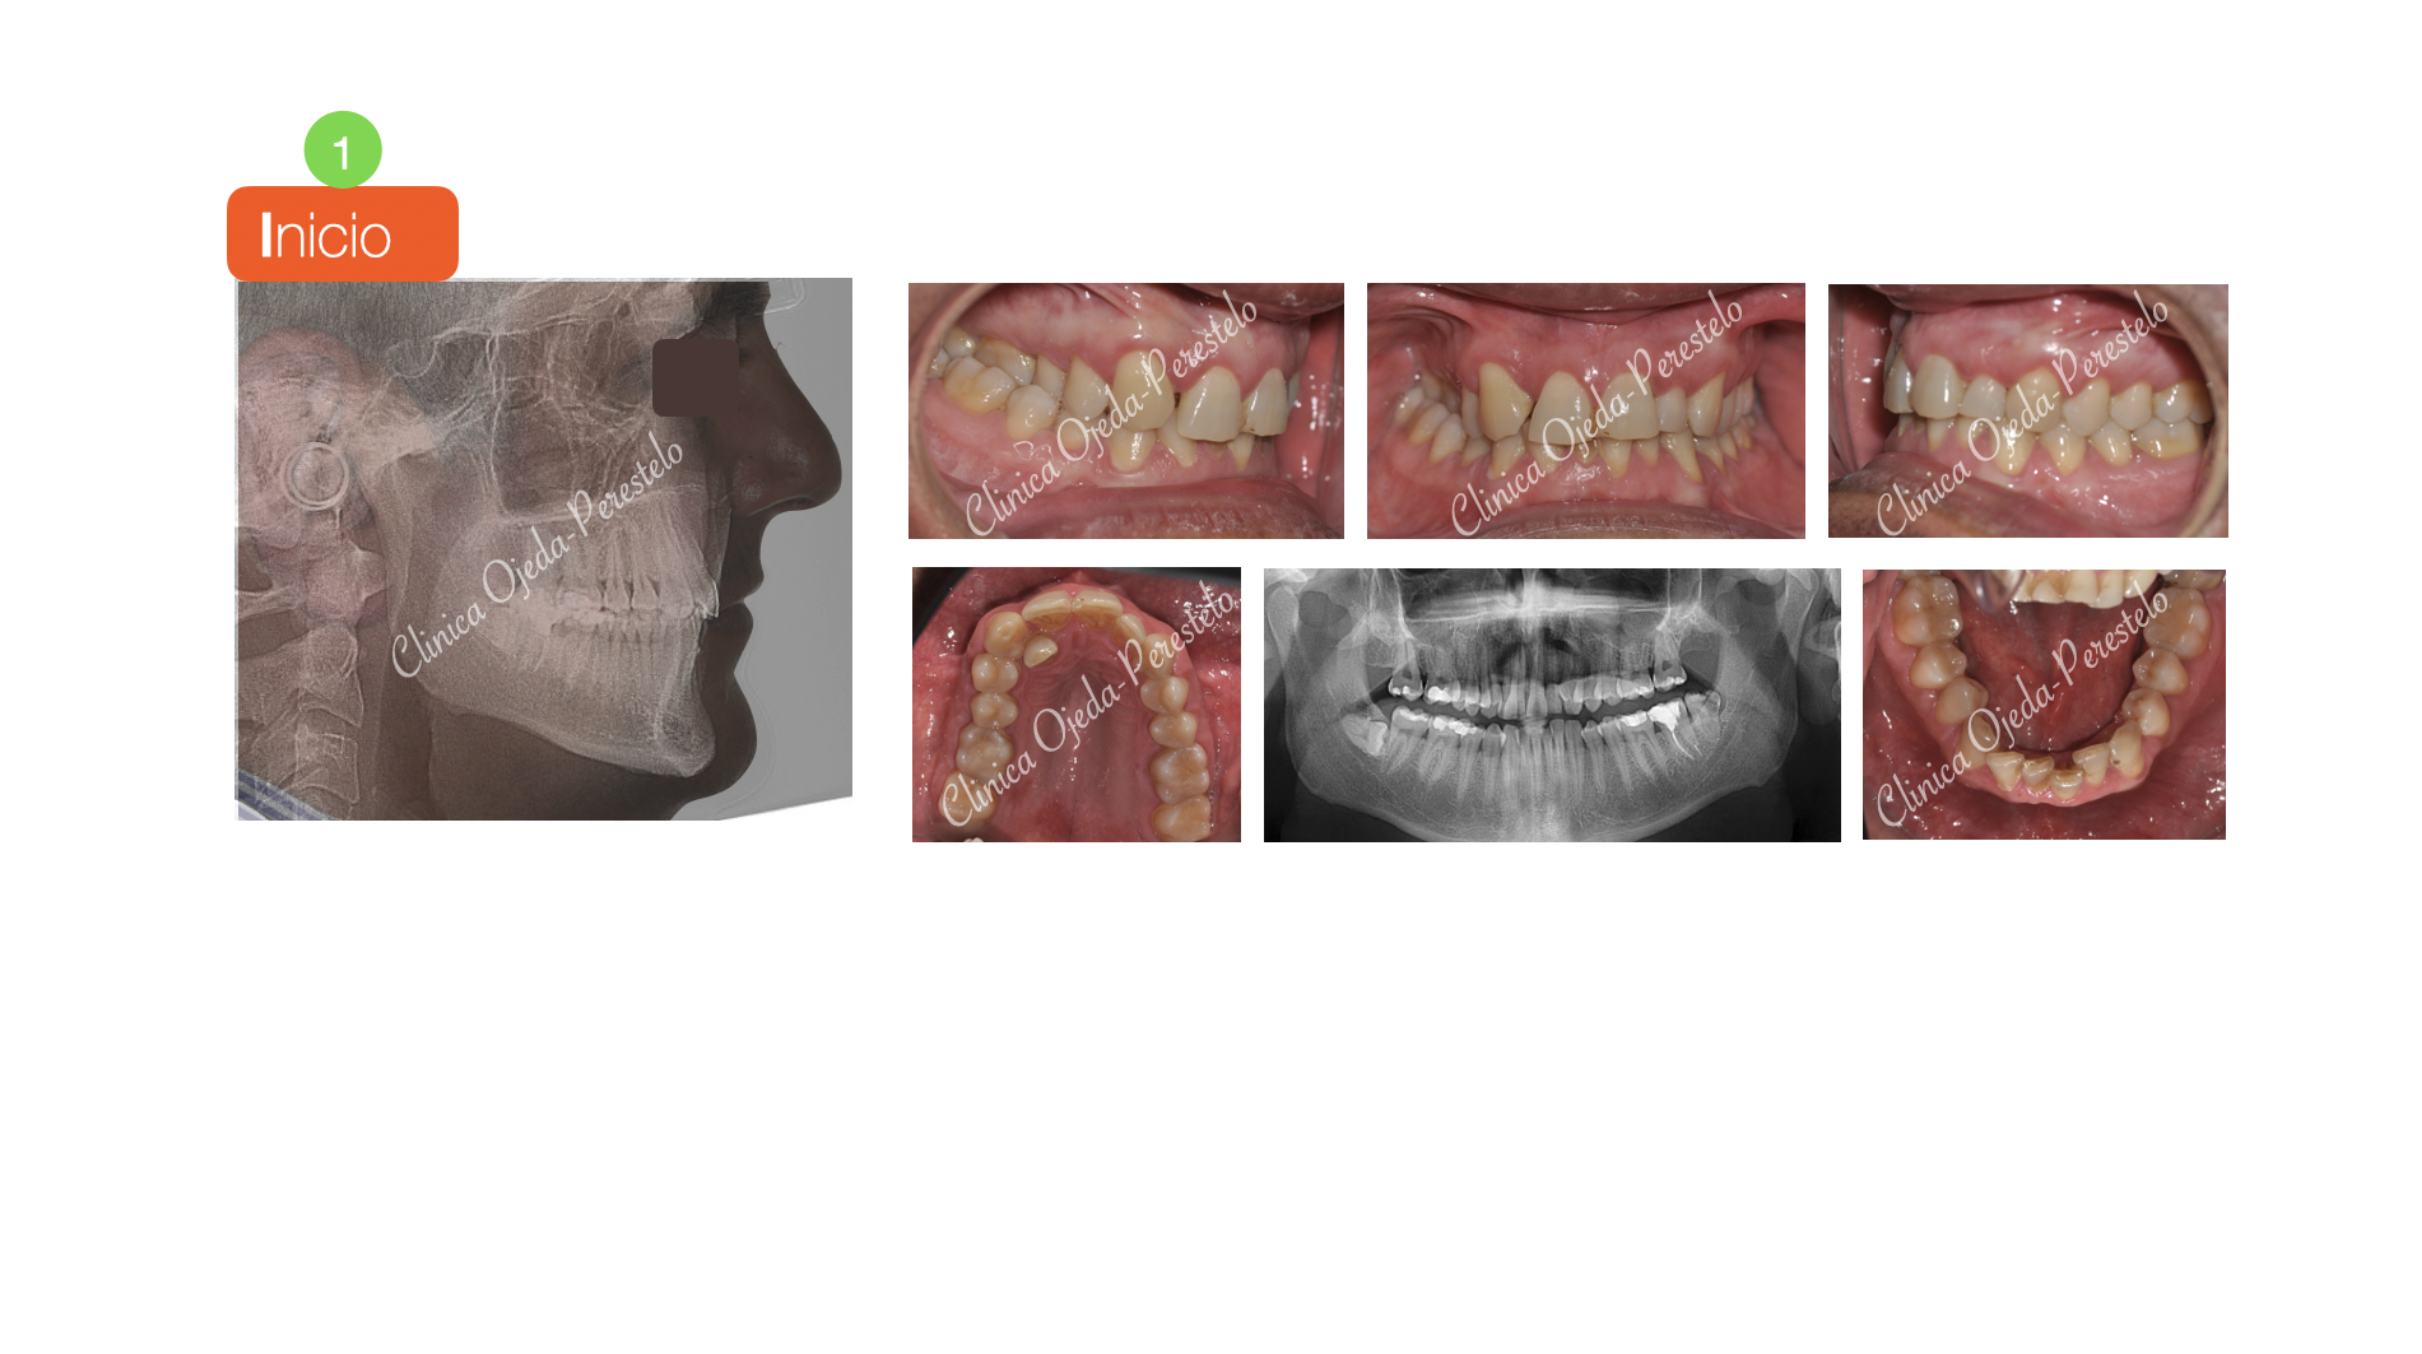

Mordida Cruzada Unilateral con Apiñamiento Severo

Los alineadores transparentes nos permiten corregir casos complejos como en este paciente con mordida cruzada y con un incisivo lateral muy palatinizado.

Queremos destacar la mejora en la amplitud de la sonrisa con un correcto engranaje dentario y centrado de las lineas medias. Todo ello se ha realizado con 147 alineadores superiores y 113 inferiores a cambio semanal combinandolo con elásticos intermaxilares. La pieza 12 presenta un pequeño remodelado del margen gingival (gingivectomia).